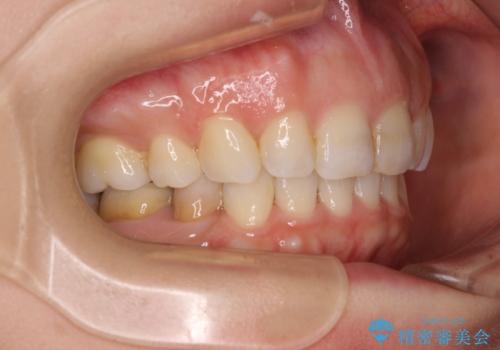

- 口元の閉じにくさと、奥歯の咬み合わせを気にして来院された患者様です。

左下の大臼歯2本が顕著に舌側に傾斜しているため、まずは奥歯の咬み合わせを改善をし、その後上下左右の第1小臼歯4本を抜歯することで口元を引っ込めながら整えることとしました。